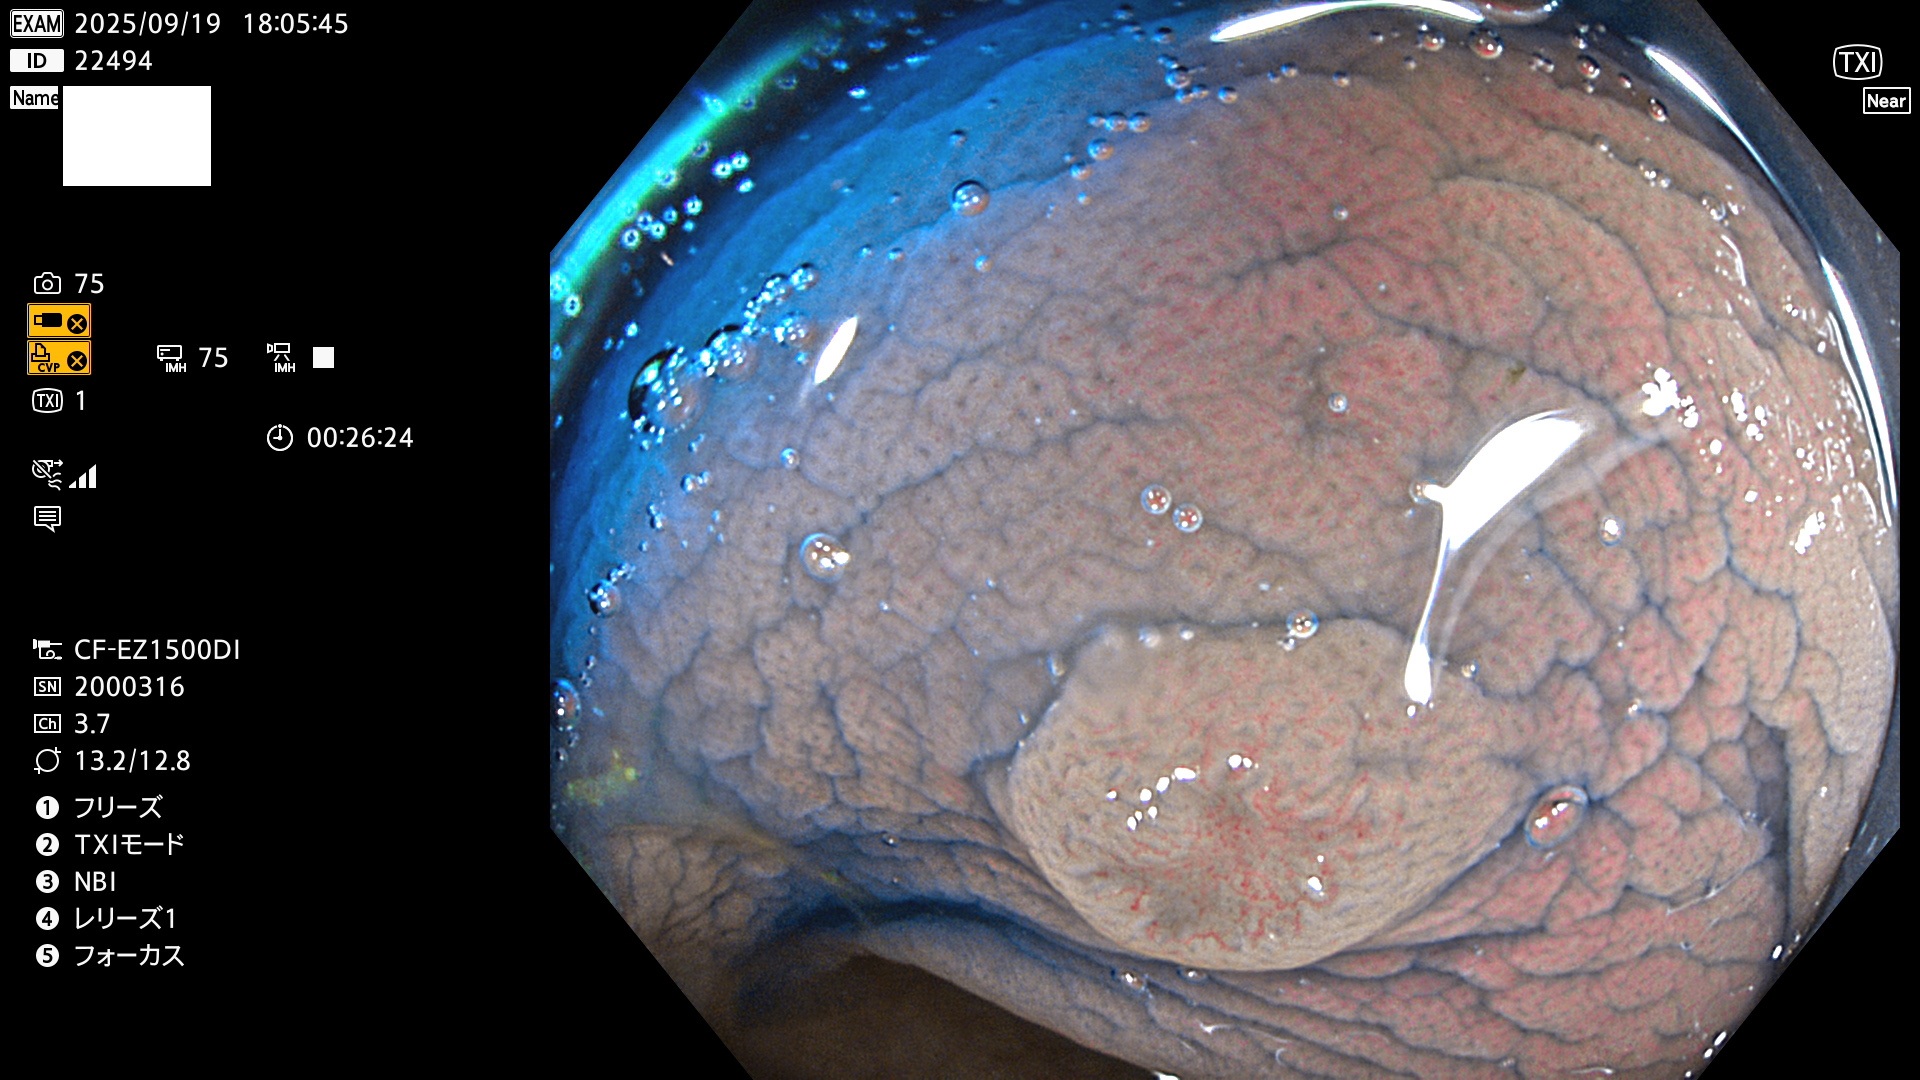

完全に平坦な物をUb、陥凹している物をUcと呼びます。Ubは認識が困難で、Ucはびらん(炎症)と紛らわしいために見落とされやすく、「内視鏡後・大腸癌」の原因になります。

専門的)Uc=De Novo癌? 内視鏡の解像度が低かった時代、このような説もありました。しかし今日の高精度内視鏡では良性の微小なUc型腺腫(APC遺伝子異常の腺腫)が日常的に見つかります。Ucこそが多段階発癌(Adenoma-Carcinoma Sequence)のMain Routeです。

毎週の検査(木・金・土・日)に発見されたUbとUc型・腺腫を、その週の日曜の夜にUPし1週間、提示します。

2025年9月17日〜9月21日の4日間(40件)6個 (Uc_ADR=6個/40人=15%)